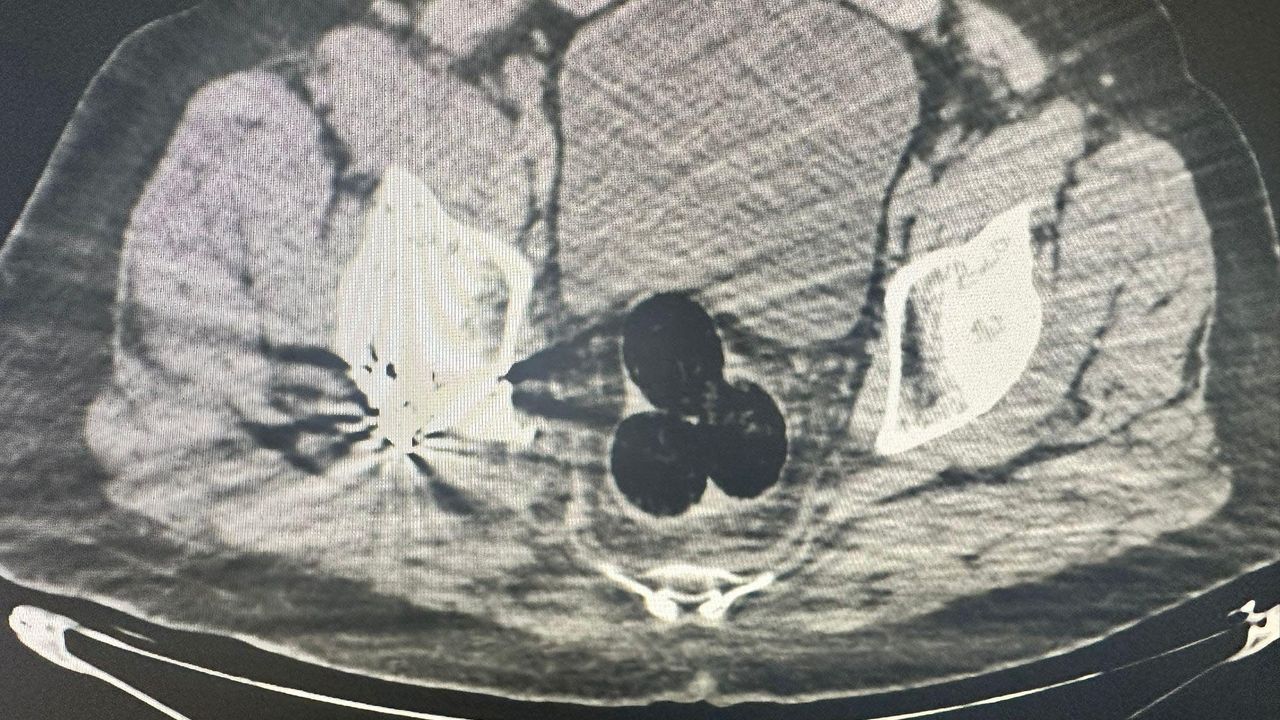

Iğdır Emniyet Müdürlüğü Narkotik Suçlarla Mücadele Şube Müdürlüğü ekipleri tarafından, İran'dan ülkeye giren bir kişi, şüphe üzerine hastaneye götürüldü. Burada yapılan radyolojik görüntülemede şüphelinin makatında 3 parça halinde yabancı cisim tespit edildi. Hastanedeki operasyonla çıkarılan 3 pakette 130 gram metamfetamin ele geçirildi. Şüpheli gözaltına alınırken, soruşturma kapsamında polis, bu kişiyle bağlantılı olduğu ve aldıkları uyuşturucuyu kentte kullanıcılara sattığı tespit edilen 2 şüpheliyi daha yakaladı. 47 gram daha metamfetamin ele geçirildi.